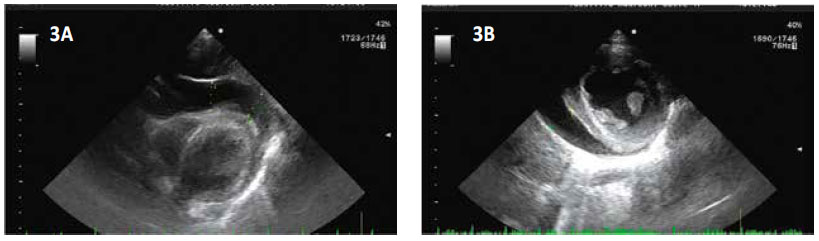

Ingresa a consultorio externo por presentar tiempo de enfermedad de 15 días con dolor de garganta, tos esporádica y cansancio, fiebre que cedía con Paracetamol; 2 días antes presenta diaforesis, malestar general y 1 día antes se agregan náuseas y vómitos más frialdad distal y dolor torácico. Es evaluado con FC: 145 x’, PA: 73/52 mmHg. taquipneico, pálido y con frialdad distal, los ruidos cardiacos con leve disminución del tono, no soplos, no visceromegalias; es referido a trauma shock de emergencia donde se le brinda fluidos en bolo Endovenoso, con dobutamina y noradrenalina. Y manejo antibiótico con ceftriaxona y macrólido Los exámenes auxiliares (Tabla 01) muestra: Hemograma leu 18410 /µL, Hemoglobina (Hb) 14.9gr/ dL, plaquetas: 322700 /µL, lactato 3.1 Ph 7.4 deshidrogenasa láctica(DHL): 1884 IU/L , alanina aminotransferasa (TGP): 1212 IU/L aspartato aminotransferasa (TGO): 1754 IU/L , creatina- fosfocinasa (CPK)total 3471 ng/ml, Troponina I: 7164 Pg/ml. IFI viral negativo, Core Total Hep B, hepatitis A IgM, hepatitis C (no reactivos) IgM para Mycoplasma Pneumonae (positivo) y Mycoplasma pneumonae (Reactivo). La Radiografía de tórax (Figura N°1) muestra leve cardiomegalia y refuerzo parahiliar derecho, el EKG (Figura N°2) se observó complejos QRS de bajo voltaje, taquicardia sinusal y leve supradesnivel del segmento ST. El ecocardiograma (Figura 3 A y B) efusión pericárdica moderada, dilatación de Vena cava inferior, pericardio engrosado, FEVI (fracción de eyección del ventrículo izquierdo) 66%, Ventrículo derecho disminuido. Con todo esto y los datos de laboratorio se establece el diagnostico de Miopericarditis.

Figura 3 A y B. Imágenes ecocardiográficas que evidencian efusión pericárdica anterior (3A), pozo de 18mm y pericardio hiperecogénico y engrosado. Y efusión pericardica posterior (3B) de iguales características pero de pozo de solo 6mm.

La ecocardiografía establece el diagnóstico correcto en el 90 % de los casos y hace posible la conducta diagnóstica y terapéutica, esto nos permitió hacer el seguimiento de la efusión pericárdica en nuestro paciente, evaluar signos de taponamiento cardiaco ya que fue una opción la pericardiocentesis, pero dada la evolución y la etiología del paciente, se desistió del procedimiento. 4